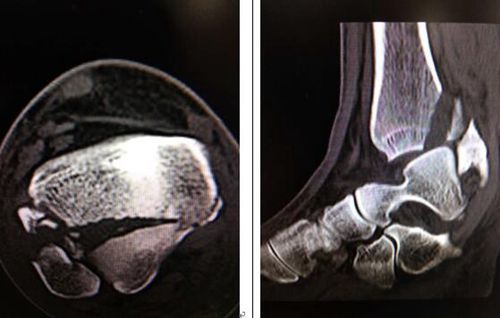

術(shù)前檢查

關(guān)節(jié)面粉碎骨折,不幸成為脛骨骨折中的3%~10%

接診后,足踝科曹廣超主任一邊比劃著一邊用英語與Matteo交流。一番詢問后,曹主任檢查發(fā)現(xiàn),Matteo右腳踝部腫脹、畸形、不能負(fù)重。CT片掃描顯示右脛骨下端粉碎性骨折,是典型的Pilon骨折!而且是比較嚴(yán)重的C3型關(guān)節(jié)面粉碎骨折!